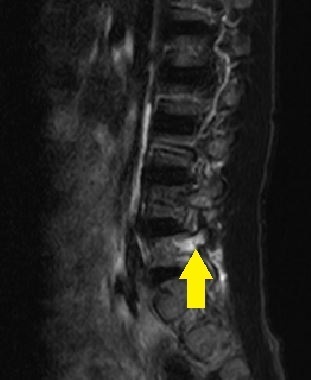

画像検査・診断について

単純レントゲン検査で椎弓・骨年齢の確認、

MRIでは腰椎分離症早期診断を、CT検査(他院依頼)では病期の判定を目的とします。

- 単純レントゲン画像 側面像

- MRI画像

- CT画像

L5左は腰椎分離症終末期